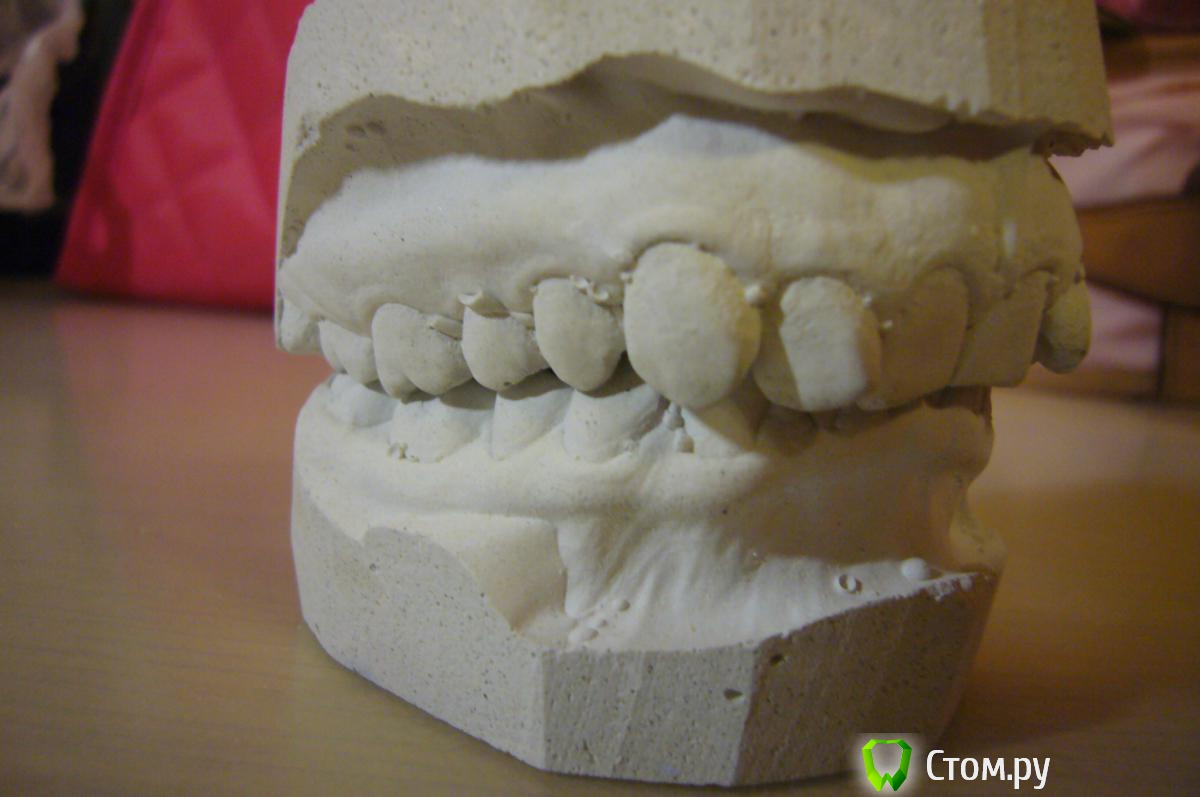

Кнопочка Опубликовано 29 июля, 2014 Автор Поделиться Опубликовано 29 июля, 2014 (изменено) Вот фото до брекетовВот зубы до брекетов,с удаленными четверкамиСлепок, правда зубы немного отколоны сбокуСнимки:и сейчас Изменено 29 июля, 2014 пользователем Кнопочка Ссылка на комментарий